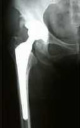

高生体活性を有するチタン合金部材(人工股関節・椎体等)